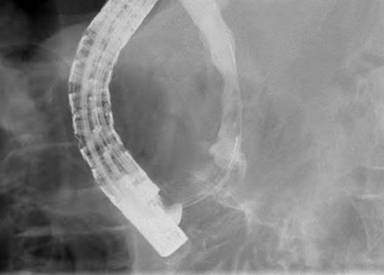

The patient was referred to the University of Colorado to establish tissue diagnosis and for an attempted endoscopic resection given his age and comorbidities. On repeat ERCP, an ampullary mass was identified involving the major papilla (Figure 1). A localized distal biliary stricture was also found which did not have the appearance of intraductal growth of an ampullary mass. Endoscopic ultrasound confirmed the presence of the ampullary mass causing a stricture (mass 2.2 cm in largest diameter; Figure 2). The stricture was in the very downstream common bile duct, felt to be entirely within the intra-duodenal portion, and EUS showed no definite submucosal invasion. Endoscopic biopsies were suspicious for adenocarcinoma, but without definite invasion; it was not felt that brushings would add any useful information at this point. After a lengthy discussion of treatment options, the patient elected for an attempt at endoscopic ampullectomy rather than proceeding directly to surgery. Endoscopic ampullectomy was performed with a polypectomy snare in multiple segments (Figure 3). Histologic analysis demonstrated periampullary/duodenal dysplasia (adenoma) associated with invasive carcinoma limited to the ampulla. Immunohistochemistry demonstrated positive staining for CK20 and CDX2 and negative staining for CK7. Based on the combined findings of duodenal dysplasia and immunoreactivity for CK20 and CDX2, the carcinoma was classified as intestinal-type. Invasive carcinoma was widely present at the cauterized tissue edges. No lymphovascular invasion was identified.

Figure 1. ERCP confirmed the presence of an infiltrative mass involving the major papilla. |